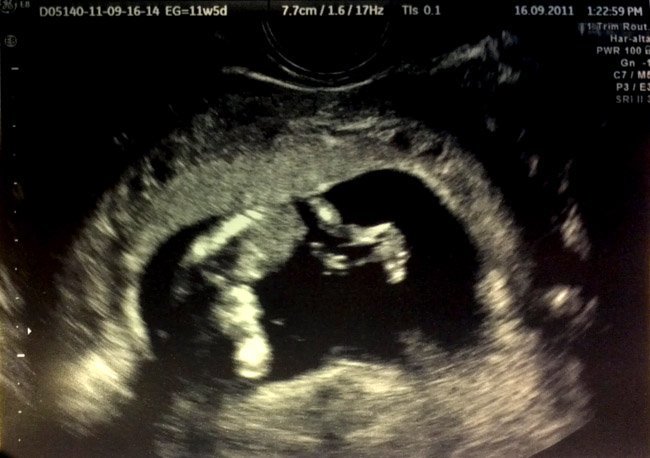

Pues bien, ahora el tercero está en camino y quiero explicaros mis primeras sensaciones. Es tan sólo un pequeño “garbancito” o quizás una “lentejita”, bueno, es más grande porque ya ronda los 6 cm, pero ya hemos podido verlo en ecografías y ya hemos podido escuchar su corazón.

Escucharlo suele ser el momento más emocionante de dicho evento, sobretodo en la primera ecografía, cuando aún tenía sólo ocho semanitas y al mirarlo no se apreciaba una forma definida. Ahora, con doce semanas, ya pudimos ver la imagen que tenéis arriba, un pequeño bebé que da sus saltitos y hasta saluda con la manita (a lo que mis hijos respondieron saludando también con la mano al monitor).